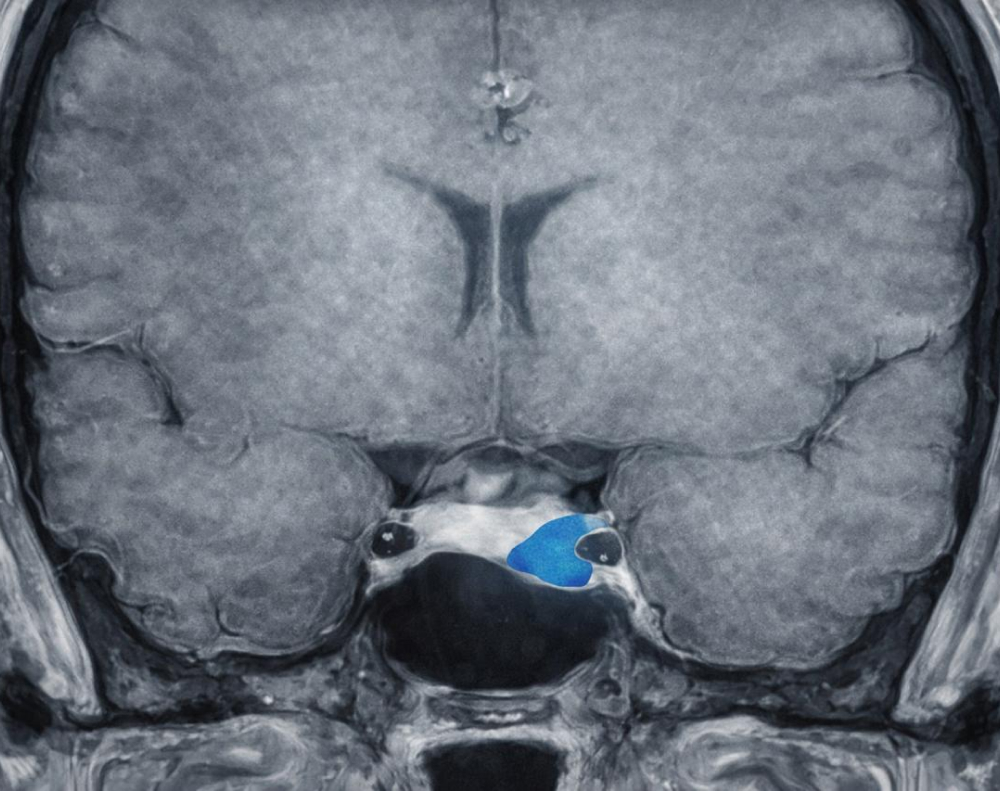

La causa más común de la acromegalia es un adenoma hipofisario, un tumor benigno en la glándula pituitaria que produce GH en exceso. En casos raros, puede deberse a tumores en otras partes del cuerpo (pulmones, páncreas o glándulas suprarrenales) que secretan sustancias que estimulan la producción de GH. Estos tumores suelen ser benignos, pero su crecimiento puede comprimir estructuras cercanas y causar síntomas adicionales como dolores de cabeza y problemas visuales.

- Imágenes. Resonancia magnética para localizar el tumor en la hipófisis y evaluar su tamaño.